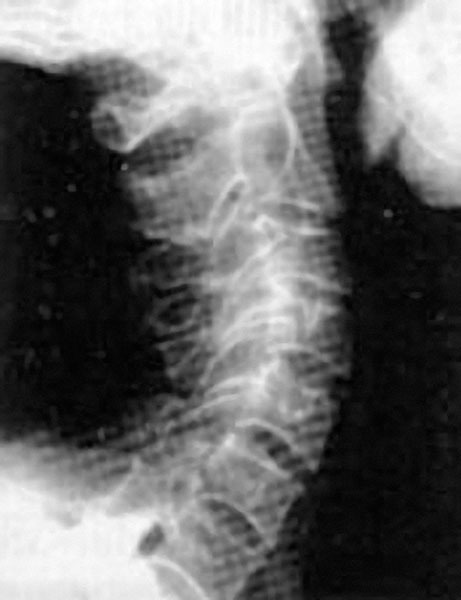

Из-за того, что с возрастом диски между позвонками уплощаются, шея укорачивается, часто весьма значительно (рис. 3).

Рис. 3. Шейный отдел позвоночника

Появление поперечных морщин и складок на боковой поверхности шеи служит точной приметой этого явления.